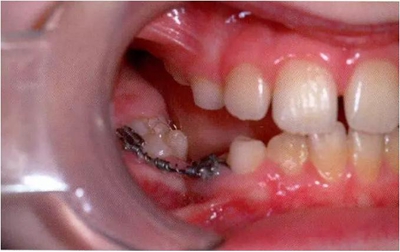

圖2:中度下沉的臨床像

圖3:重度下沉的臨床像